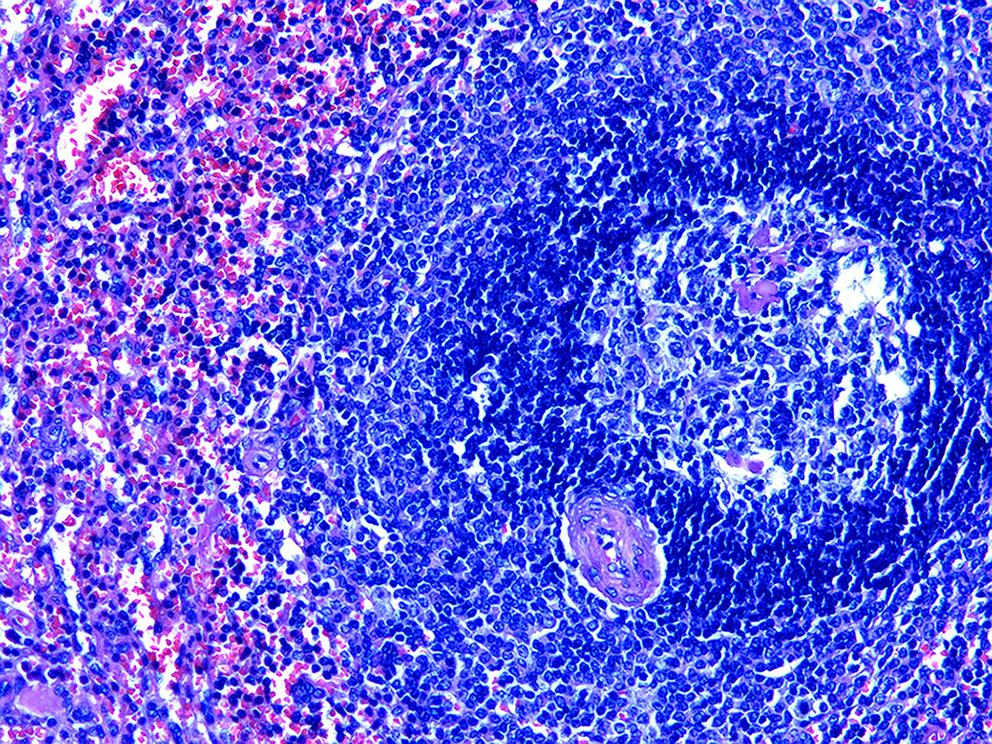

Misdiagnosis of intrapancreatic accessory spleen: A report of two cases

Mengzhe ZHANG, Jie RAO, Zhengle ZHANG

2024, 40(2): 365-368. DOI: 10.12449/JCH240223

Abstract(1384) HTML (333) PDF (1188KB)(176)

Abstract:

Accessory spleen refers to the spleen tissue that exists outside of the normal spleen, with a similar structure to the main spleen and certain functions. Intrapancreatic accessory spleen (IPAS) completely enveloped by the pancreas has an incidence rate of only 2%, and it is easily misdiagnosed in clinical practice due to its atypical clinical symptoms and similar radiological features to pancreatic neuroendocrine tumor, pancreatic solid pseudopapillary tumor, and other pancreatic space-occupying lesions. This article reports the clinical data of two patients with IPAS who were misdiagnosed as pancreatic neuroendocrine tumor and pancreatic solid pseudopapillary tumor, respectively, analyzes the reasons for misdiagnosis, and summarizes the experience in diagnosis and treatment, in order to improve the ability for the differential diagnosis of IPAS in clinical practice.